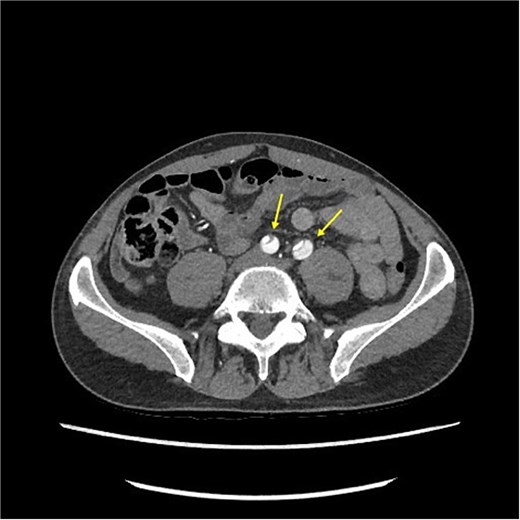

CT angiography revealed a Type A aortic dissection, stretching from the aortic valve to the femoral arteries, with cessation of blood flow halfway down the femoral artery and distally (Figs 1 and 2). An acute echocardiogram showed a dilated aortic sinus (42 mm) and ascending aorta (53 mm), with moderate aortic insufficiency. During these investigations, the patient was stable, awake, and without pain. Thrombolytic treatment was stopped immediately, and systolic blood pressure was kept <110 mmHg by labetalol and nitroglycerin.

CT-scan pre-operatively showing Type A aortic dissection from the ascending aorta to the femoral arteries.